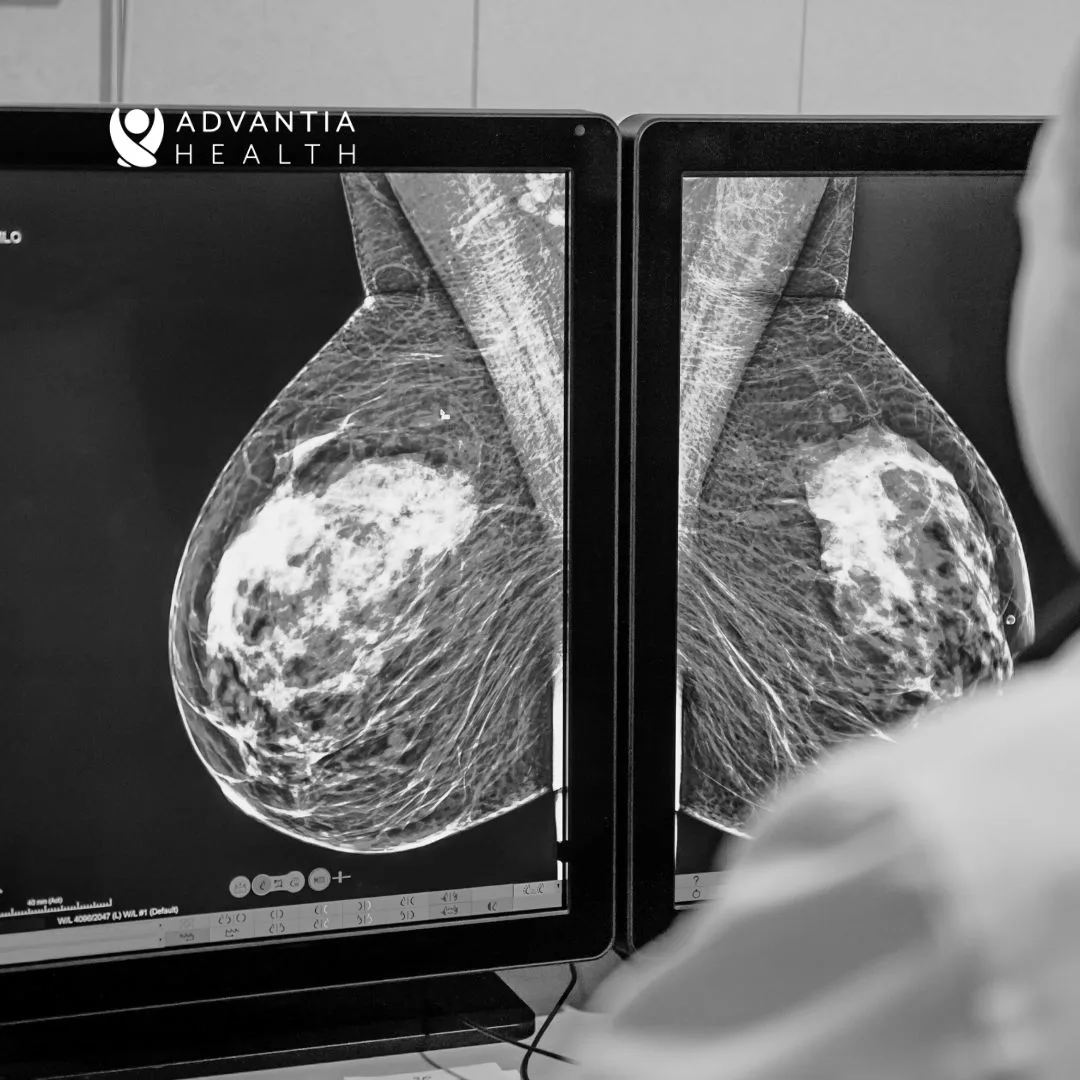

Breast health is a critical aspect of overall well-being, and early detection is paramount in the fight against breast cancer. While breast cancer remains a significant health concern for women, advancements in imaging technology have played a pivotal role in enhancing the accuracy of mammograms, making early detection more effective and reliable.

The history of imaging technology began with traditional screening mammography, which involved the use of X-ray films to capture images of the breast. While this was an important step forward in early breast cancer detection, the technology had limitations, particularly in imaging dense breast tissue. As the need for more accurate and detailed imaging became evident, the transition to digital mammography marked a significant milestone. Digital mammography brought forth clearer and more precise images, enhancing the ability to detect abnormalities in breast tissue.

Subsequently, the development of digital breast tomosynthesis (DBT) presented a groundbreaking shift in mammography technology. Unlike traditional mammography, DBT captures multiple images of the breast from different angles, reconstructing a three-dimensional image of the breast tissue. This advancement has been particularly beneficial for women with dense breast tissue, as it significantly reduces the overlapping of breast structures that could potentially obscure early signs of breast cancer.